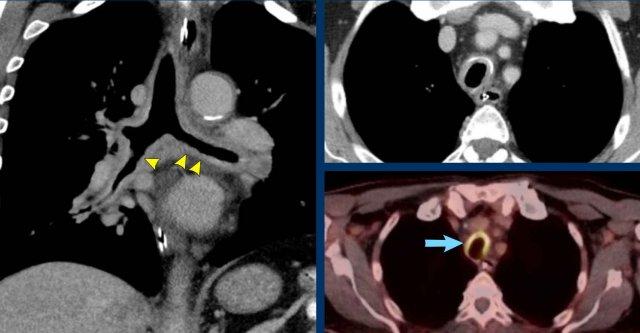

Hình ảnh

Khối bờ rõ ở phế quản gốc trái ở nam giới 39 tuổi.

Tiếp tục xem PET-CT…

PET-CT 68Ga-Dotatate cho thấy hấp thu mạnh, xác nhận nguồn gốc tế bào thần kinh nội tiết.

U carcinoid xuất hiện ở các đường thở trung tâm hơn (mặc dù hầu như không bao giờ ở khí quản) cũng như ở các đường thở ngoại vi hơn, kéo dài đến tận một phần ba ngoài của phổi.

Trên CT, u carcinoid là tổn thương bờ rõ, thường tăng tỷ trọng trên CT sau tiêm thuốc cản quang do bản chất tăng mạch máu.

Vôi hóa có thể gặp trong một số ít trường hợp.

Các thay đổi sau tắc nghẽn thường gặp do tắc nghẽn lòng đường thở, và có thể là lý do phát hiện bệnh.

Một số tổn thương cũng có thành phần ngoài lòng đường thở, điều này loại trừ khả năng điều trị triệt căn hoàn toàn qua thủ thuật nội soi.